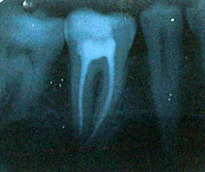

Endodonti (Kanal tedavileri,fiber post uygulamaları)